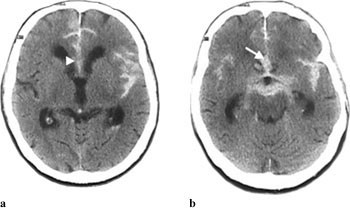

Subaraknoidalblødning ble påvist ved CT-undersøkelse hos 64 av 70 pasienter (91 %). Blod ble hyppigst påvist i basale cisterner (75 %), i fissura Sylvii (73 %) og i cerebrale kortikale sulci (67 %) (tab 1, fig 1 – 5). Funn forenlig med økt intrakranialt trykk (utvidet ventrikkelsystem, spesielt sideventriklenes temporalhorn og/eller overskyvning av midtlinjestrukturer, endret form av basale cisterner, utvisket overflaterelieff og/eller periventrikulært ødem) ble påvist hos 26 pasienter (41 %).

Opplysninger vedrørende cerebral angiografi forelå hos 64 av 70 pasienter med subaraknoidalblødning. Av disse hadde ti (16 %) normalt funn. Til sammen 63 aneurismer ble påvist hos 52 pasienter (81 %). Intracerebral arteriovenøs malformasjon ble påvist hos to pasienter. Hos seks pasienter ble det gjort samtidig funn av henholdsvis fire (n = 2), tre (n = 1) og to (n = 3) aneurismer ved samme undersøkelse. Aneurismer ble hyppigst påvist på a. cerebri media, a. communicans anterior og a. carotis interna (tab 2). Påvisning av blod i subaraknoidalrommet kunne gi indikasjon på lokalisering av aneurismet (tab 2, fig 2, fig 4). Prediksjon for påvisning av lokalisasjon av blødende aneurisme var kun meget god for aneurismer på a. cerebri media, hvor 12 av 13 aneurismer ble lokalisert korrekt. Det var dårligere prediksjon for aneurismer lokalisert til a. communicans anterior og a. carotis interna, med henholdsvis 11 av 18 og fire av ti aneurismer riktig lokalisert. Angiografi var utført hos åtte av ti pasienter med blod i septum pellucidum, og hos samtlige ble det påvist aneurisme på a. communicans anterior (fig 4). For de andre lokalisasjonene var det få observasjoner og lav treffsikkerhet.

Cerebral CT vil ofte kunne gi informasjon om lokalisering av aneurismet som ligger til grunn for blødning (8). Tidligere studier har vist at treffsikkerheten for lokalisering av aneurisme ut fra CT-undersøkelse kun var høy ved ruptur av aneurismer lokalisert til a. communicans anterior og a. cerebri anterior (15, 16). I vår studie fant vi høyest treffsikkerhet når det gjaldt blødning fra aneurisme på a. cerebri media, også med riktig sideangivelse, mens treffsikkerheten med hensyn til blødning fra aneurisme på a. communicans anterior var dårligere. Septum pellucidum-hematom er ansett som et sikkert tegn på aneurisme på a. communicans anterior (8), og dette ble bekreftet i vår studie. Derimot vil ikke alle aneurismer lokalisert til a. communicans anterior blø til septum pellucidum. Enkelte angir at blod i fissura interhemisphærica er et sikkert og hyppig tegn ved aneurismer på a. pericallosa, men dette var ukjent for oss da bildene ble gjennomgått. Lokalisering av blødende aneurisme før radiologisk eller kirurgisk sikring er spesielt viktig når det foreligger flere aneurismer. Multiple aneurismer, vanligvis to eller tre, kan finnes hos 20 – 30 % av pasienter med intrakraniale aneurismer (17). I akutte situasjoner kan det hende at pasientens tilstand ikke tillater den tidsbruk som går med til angiografi. En ”nødoperasjon” er helt avhengig av at CT viser og kan tolkes med størst mulig sikkerhet med hensyn til lokalisasjon.